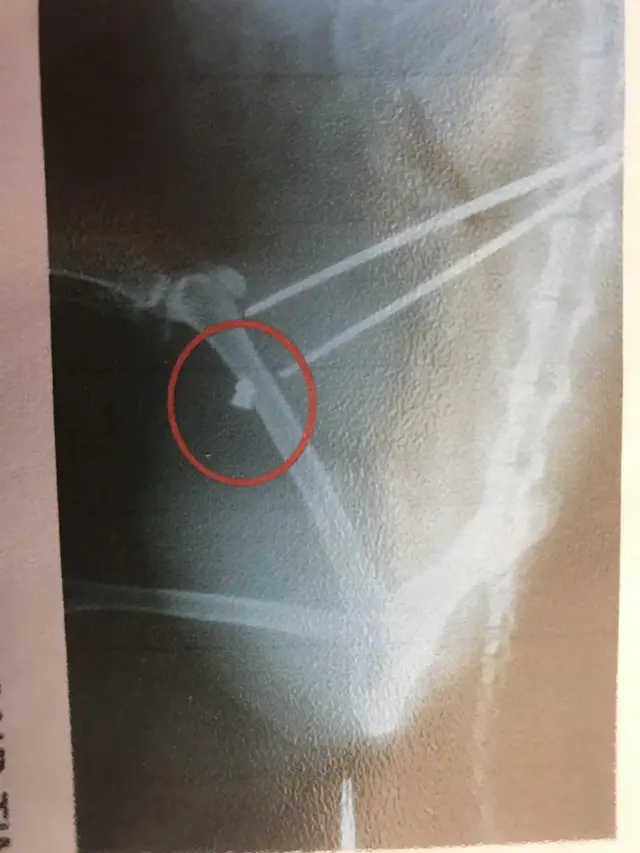

Image source, RSPCAA pet cat who was shot twice with an air gun was left in "considerable pain".

The black and white cat called Nev was found collapsed on his owners’ patio in Henstridge in Somerset, with a wound on his leg.

His owners took him to the vets where the pellet was removed.

An x-ray showed the cat had been shot previously and the pellet was still embedded inside his leg.

RSPCA Inspector Ken Snook said: “This poor cat has been cruelly shot with an air gun and would have been in a considerable amount of pain.

"It was a shock for the owners to find Nev had been shot not once but twice."